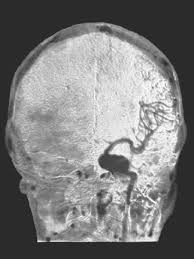

Cerebral aneurysm images